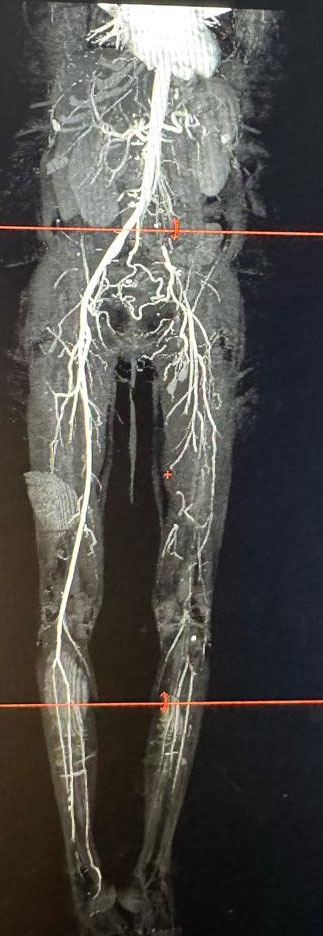

When she came to the Vascular Surgery Department, her left leg had color changes of the skin up to the lower 3rd of the leg, hypothermia till mid leg, flickers of movement at the ankle and absent left lower limb pulses. CT angiogram of the lower limb demonstrated thrombus in the iliac artery, occluded common and superficial femoral arteries and scant reformation of the tibial arteries. The prognosis was explained to the patient and attenders and emergency femoral and if needed, popliteal thrombectomy was offered as a last-ditch effort to save the leg. As the presentation was very much delayed, high probability of failure and need for major amputation were stressed upon.

The image shows the CT angiogram of the patient showing occluded iliac and femoral arteries. The tibial arteries are poorly visualized as well. Note the relatively well-preserved right-side vasculature.